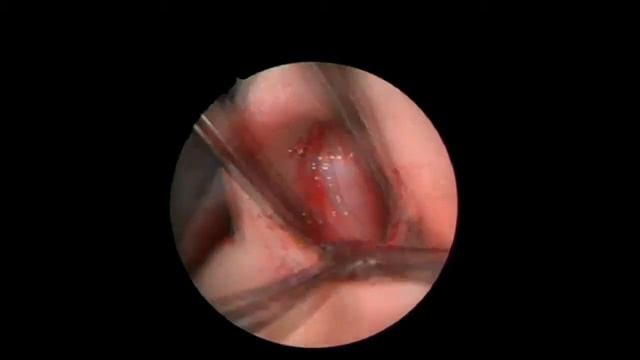

Эндоскопическая септопластика( кристотомия).Врач Антипова Ю.А.